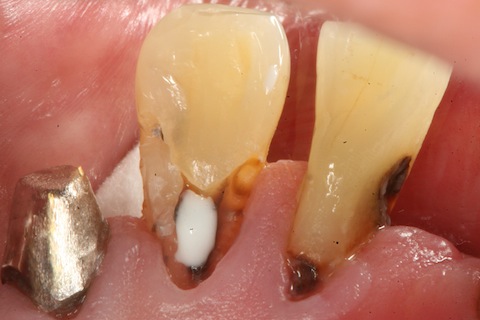

70代男性、右下3、歯根面カリエス。

義歯が入っており、象牙質だけが虫歯になるタイプ。

臨床的にはよく見かけるのだが、

その原因はよく分かっていない。

軟化象牙質を全部除去する必要はない。